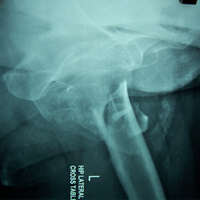

Case:7 Fracture Neck Femur with Implant failure and Re-Fixation with hemi-arthroplasty

Alcoholic Gardener by profession had slipped in bathroom & fell. He sustained fracture neck femur.He was operated with closed reduction & CC Screw fixation under IITV. Two weeks’ post fixation he again fell & sustained fracture in sub trochanteric region. He was treated with Hem-Arthroplasty with Tension band wiring.

Pre-Op

Post-Op